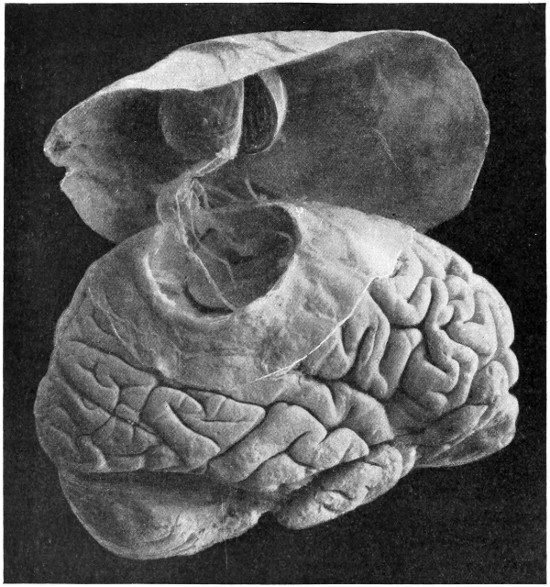

| 63. A sarcoma of the brain | 211 |

| 64. An endothelioma of the dura mater | 212 |

| 65. A fibroma of the dura mater | 212 |

| 66. An acoustic tumour | 213 |

| 67. Symmetrical tuberculomata | 214 |